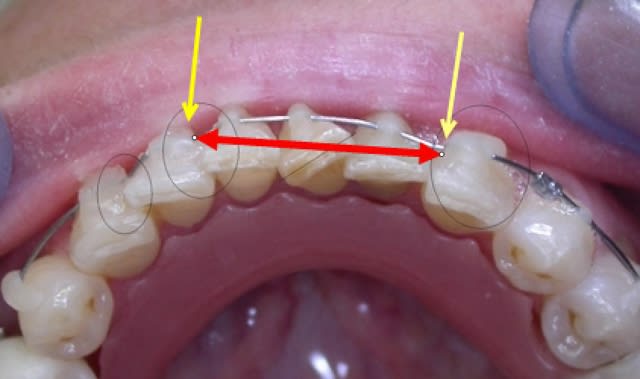

Mon premier cas en Danchamon....patiente adulte avec des dents minuscules...mes attaches étaient trop grosses!!

J'ai un peu galéré car pas de composite vraiment fluide, mais depuis j'y ai remédié.

Patiente ravie : esthétiquement ( c'est 10 fois plus joli que mes attaches esthétiques super chères!!!) et manifestement super confortable.

Moi je la revois aujourd'hui après un mois...et j'ai remis des points de colle pour "activer" l'arc ....et je me pose des questions sur la possibilté de réaligner 41

Juste un petit soucis : en rajoutant deux "points de colle", tu empêches le fil de glisser, la distance entre ces deux points est figée. Tu ne peux plus corriger les rotations parce que les dents sont les unes par dessus les autres. Tu es bloquée.

Effectivement j'ai bien pensé que j'allais figer l'arc, je l'ai déjà fait une fois avec une contention collée linguale sur un encombrement, et j'avais obtenu un alignement avec ouverture de diastème ( mais j'avais dès le début la longueur de fil nécessaire à l'alignement, ce qui n'est à priori pas le cas ici....)